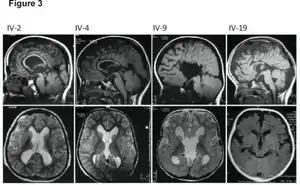

![]() | |

| MRI images showing megalencephaly in four family members who all have unusually large skulls (the family is affected by an autosomal recessive syndrome caused by a KIF7 mutation that induces multiple epiphyseal dysplasia)[1] | |

A mutation in the PI3K-AKT pathway is believed to be the primary cause of brain proliferation and ultimately the root cause of megalencephaly. This mutation has produced a classification of brain overdevelopment that consists of two syndromes including megalencephaly-capillary malformation (MCAP) and megalencephaly-polydactyly-polymicrogyria-hydrocephalus (MPPH).[4] Megalencephaly is usually diagnosed at birth and is confirmed with an MRI.

A neurological exam will then be performed using the technology of an MRI machine in order to confirm the diagnosis of megalencephaly. These imaging tests give detailed information regarding brain size, volume asymmetry and other irregular developments linked with MCAP, MPPH and hemimegalencephaly.[2][20]